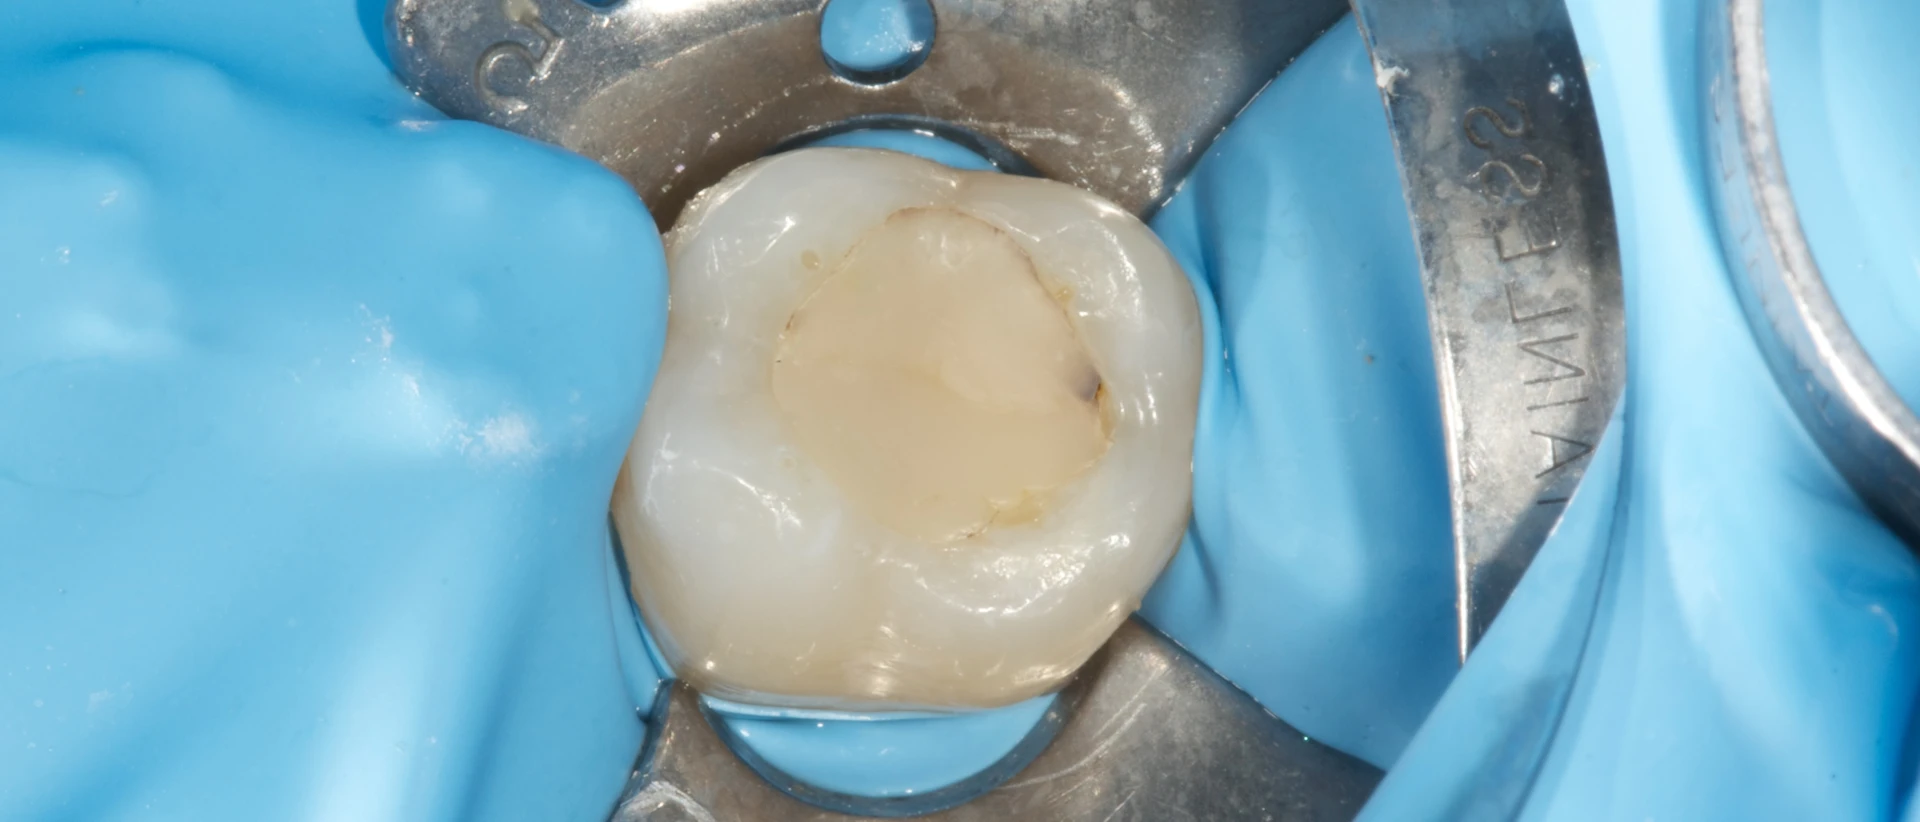

除了永久性牙齿填充物的问题外,我们也不要忽视临时填充物是否已经脱落。临时填充物更容易损坏或缺失,但即使它们是暂时的,您也应该告诉您的牙医。

这是很重要的,因为我们经常用临时填充物来封闭接受根管治疗的牙齿,我们不希望打开的根管被唾液中的细菌感染。